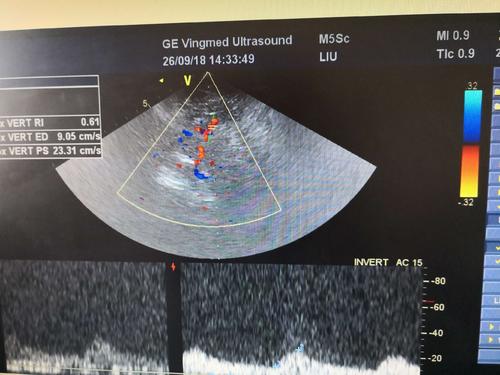

經顱彩色編碼雙功能超聲,區別于經顱多普勒超聲,它的英文簡稱是TCCD,后者是TCD。TCCD成像模式是什么樣的,tcd廠家澳思泰今天來分析這一問題。

TCCD成像模式

(1)依據多普勒頻移值編碼成像即f-TCCD:

依賴運動紅細胞所產生的多普勒頻移值進行計算機編碼,可以顯示血流方向和測算血流速度,需要校正多普勒取樣角度,角度及篩查深度依賴性較大,較易產生運動偽像。

(2)依據運動紅細胞所產生的總能量進行編碼成像即p-TCCD:

只與運動紅細胞所產生的總能量有關,無需校正多普勒取樣角度,對于受取樣角度影響較大血管病變,諸如大腦后動脈(PCA),大腦中動脈(MCA)M2段,大腦前動脈(ACA)A1段有一定的幫助作用,信噪比更高,不易產生混疊效應。p-TCCD相對f-TCCD而言,缺點是不能顯示血流方向,對顯示狹窄處高速血流敏感性較低。